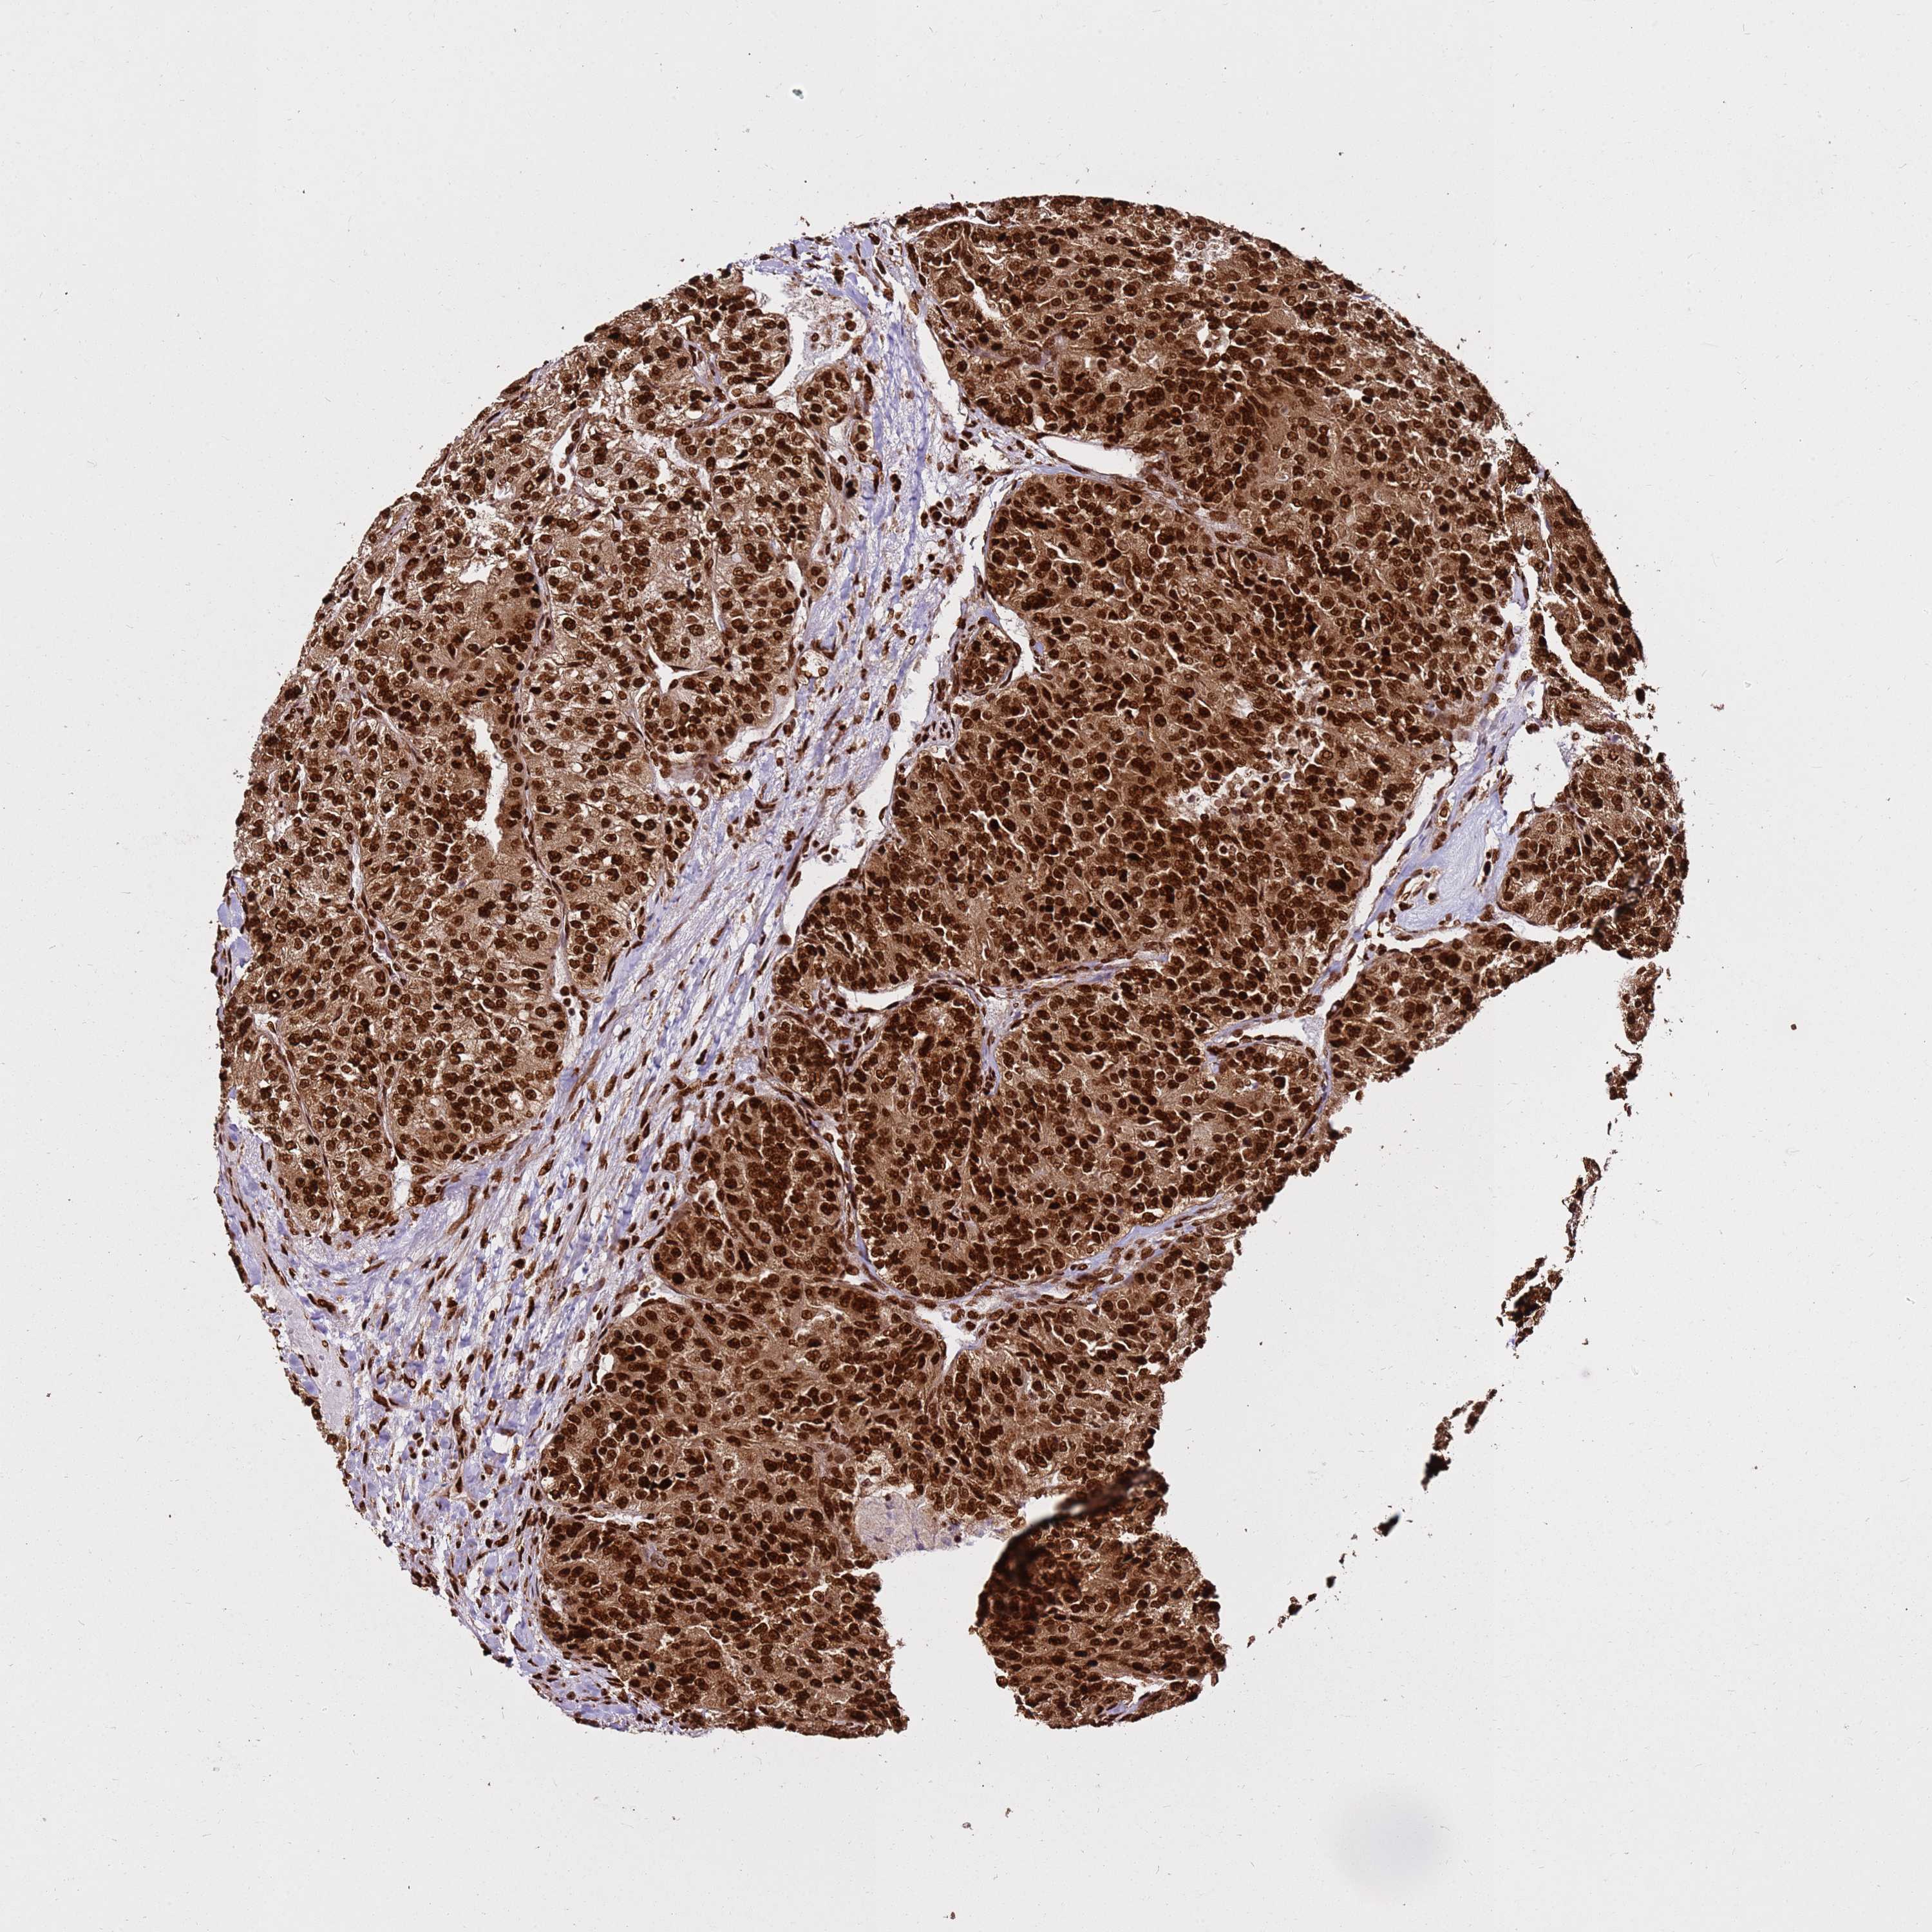

CANCER RENAL CANCER Show tissue menu

KICH TCGA KIRC TCGA KIRC VALIDATION KIRP TCGA PROTEIN RCC CPTAC PROTEIN EXPRESSION